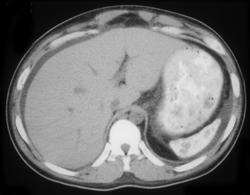

Splenic and Hepatic Cysts